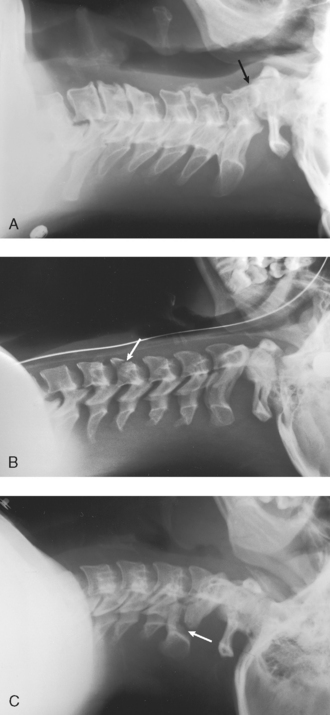

Structures shown: This projection shows the seven cervical vertebrae, including the base of the skull and the soft tissues surrounding the neck (Fig. 28-27).

Fig. 28-27 Mobile lateral cervical spine radiographs performed at the patient’s bedside several weeks after trauma. A, Entire cervical spine shows slight anterior subluxation of the dens on the body of C2 (arrow). B, Entire cervical spine shows nearly vertical fracture through the body of C5 with slight displacement (arrow). C, First five cervical vertebrae show vertical fractures through posterior aspects of C2 laminae (arrow) with 4-mm displacement of the fragments. Earlier radiographs showed that C6 and C7 were unaffected and did not need to be included in this follow-up radiograph.